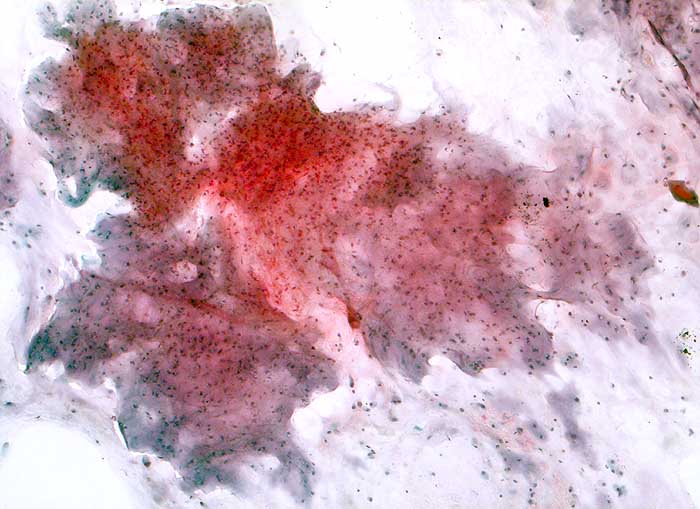

Bronchialsekret: Reichlich wolkige Matrix. Die einzeln in der Matrix eingebetteten Chondrozyten sind zahlreicher als in normalem Knorpel.

Histologische Diagnose: Ueberwiegend hoch differenziertes Chondrosarkom (Chondrosarkom

Grad I bis II) der rechten Thoraxwand mit Infiltration der dorsalen, pulmonalseitigen Resektionsfläche